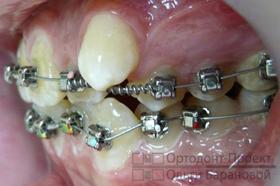

Врач-ортодонт поставил диагноз: скученность зубов на верхней челюсти. Рекомендуется установка брекет-системы Damon, которая отличается наличием двух пазов в замке брекета. На одной из стадий терапии доктор применит две дуги: первая будет отвечать за движение клыков, а вторая – за фиксацию резцов, чтобы избежать их смещения под воздействием клыков. Металлические брекеты Damon представляют собой современное и оптимальное решение. Их главные преимущества заключаются в доступной цене, компактных размерах и высокой эффективности, при условии правильного расчёта со стороны врача.

Стратегия лечения состоит из нескольких этапов: последовательная установка брекетов, расширение верхней челюсти для создания пространства, перемещение выступающих клыков на освободившиеся места с поддержкой резцов, использование ортодонтических эластиков для формирования точных межзубных контактов, а также период ретенции, чтобы закрепить результаты после снятия брекетов.

На текущем этапе ортодонтического лечения использование брекетов сфокусировано на расширении зубного ряда в области второго и четвертого зубов, при этом на системе установлены специальные пружины.

Через пять месяцев начинается новый этап — возвращение клыков на их естественное место в зубном ряду. Вторая дуга обеспечивает стабильное положение передних резцов.